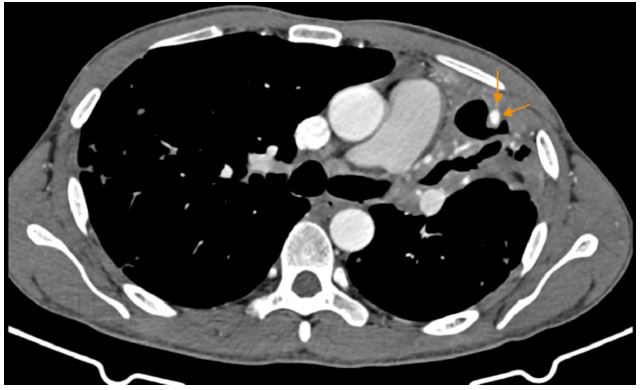

A 39-year-old male with a history of discontinued pulmonary tuberculosis treatment one year prior was admitted for hemoptysis. A few days before admission, he experienced intermittent episodes of hemoptysis, with the most significant bleeding estimated at 30-50 mL. No treatment had been initiated at that time. Chest Computed Tomography (CT) revealed a cavitary consolidation in the left upper lobe, with a 5 × 4 mm pseudoaneurysm located at the peripheral wall of the cavity. There was also evidence of a dilated left bronchial artery and hypertrophied intercostal and subclavian artery branches.

Figure 1: Cavitary consolidation in the left upper lobe. A 5 × 4 mm pseudoaneurysm is seen within the cavity wall (arrow). Dilated bronchial artery, along with hypertrophied and dilated left intercostal and subclavian artery branches, are also noted.